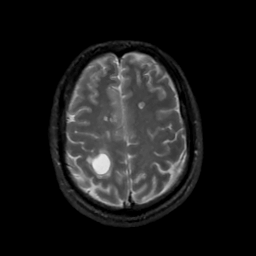

MR Study #6, March 17, 1991 -- Slice #38

[Home][Help][Clinical][Tour 1][Tour 2] Slice 38